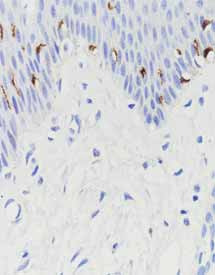

产品名称:MHA

产品编号:MAB-0128

阳性部位:细胞质

图片描述:

阑尾,MHA染色,细胞质阳性。